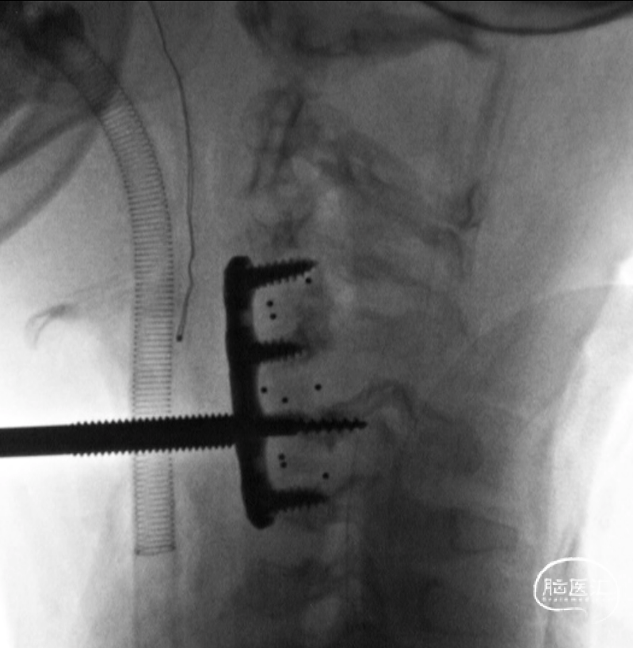

C5椎体内置入提拉螺钉,穿透椎体后壁,达到最佳提拉复位力量

旋转提拉套筒,显示C5椎体进一步向前复位